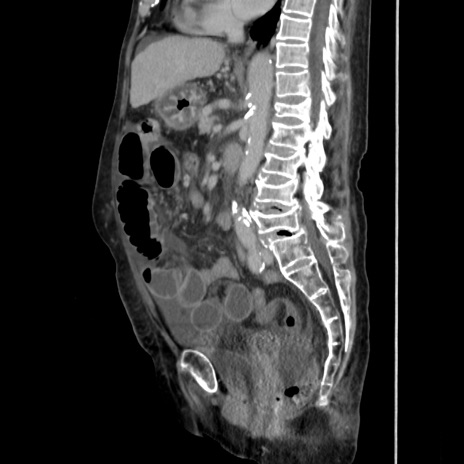

症例31(矢状断像)

【症例】80歳代 女性

【主訴】腹部膨満感

【現病歴】他院にて肝硬変にてフォロー中。1週間前から便秘、腹部膨満感、臍部腫瘤あり受診となる。

【既往歴】肝硬変

【身体所見】腹部膨隆あり、皮膚変化なし、疼痛なし。

【データ】WBC 4600、CRP 0.25